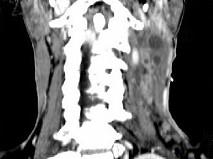

问题 男,67岁,口咽部异物感约8个月,伴口咽部疼痛,患者无明显发热.如图所示最可能的诊断为()

选项 A.扁桃体结核伴淋巴结转移 B.扁桃体脓肿伴淋巴结转移 C.扁桃体癌伴淋巴结转移 D.扁桃体淋巴瘤 E.下咽癌伴淋巴结转移

答案 C